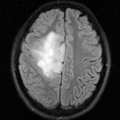

200 × 200 pixel

File size: 24 KB

MIME type: image/png

The file "RegLib27_FLAIR.png" has 1 identical duplication.

- RegLib27 FLAIR.png . . Meier (talk | contribs) . . 14:25, 20 May 2010

- RegLib27 FlAIR.png . . Meier (talk | contribs) . . 14:21, 20 May 2010